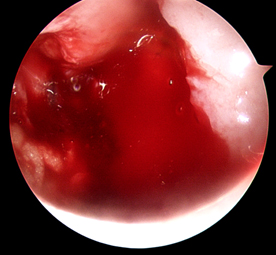

Step 1:

Cartilage injury identified